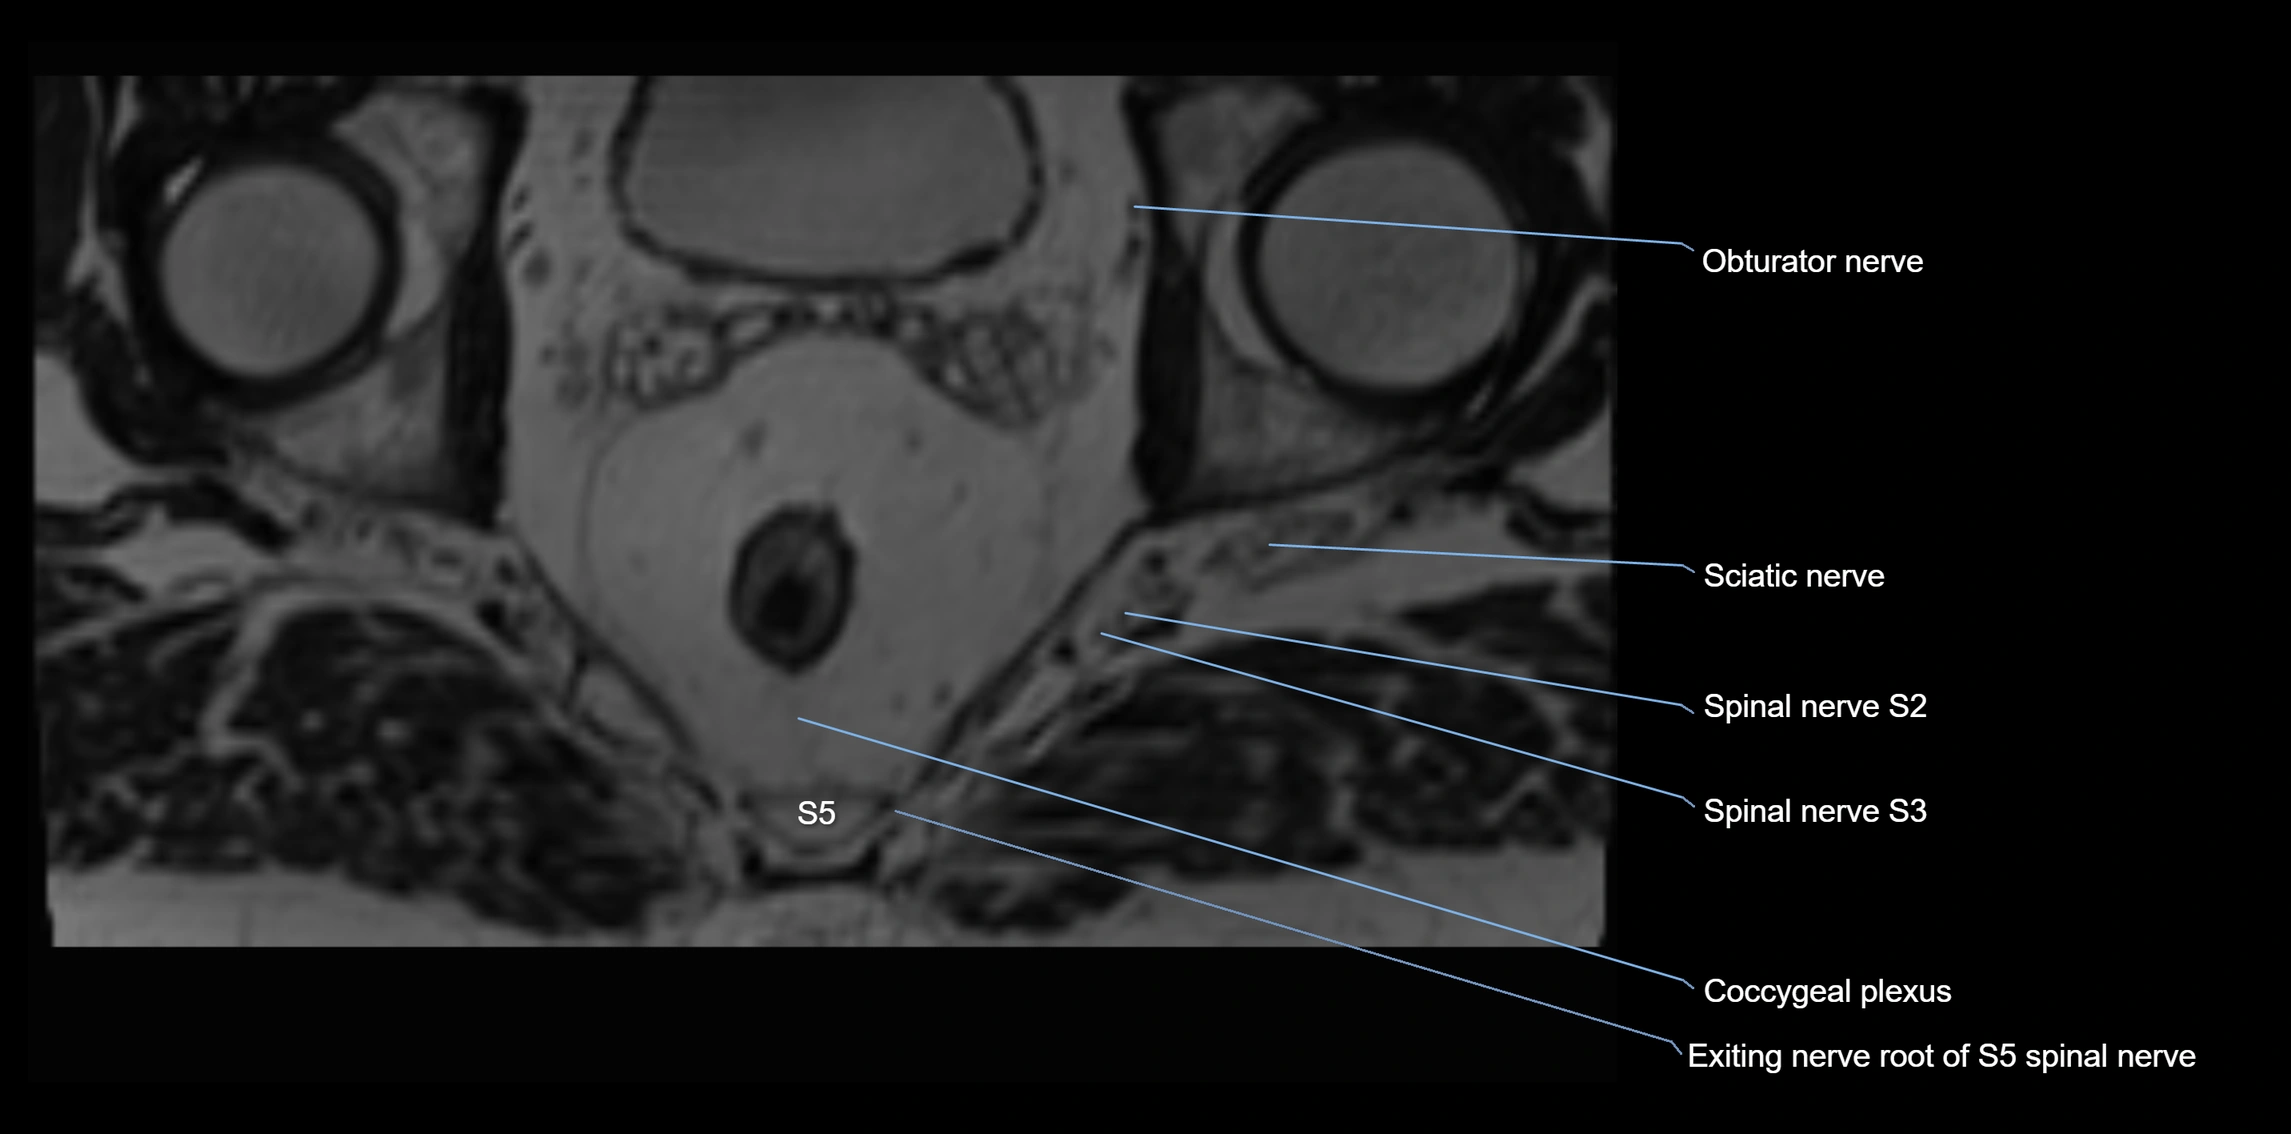

MRI Appearance

T1-weighted images:

• Nerve appears as a very thin low-to-intermediate signal intensity structure

• Surrounded by bright fat, aiding visualization

T2-weighted images:

• Nerve shows intermediate to mildly hyperintense signal compared to muscle

• Pathological involvement appears brighter

STIR (Short Tau Inversion Recovery):

• Normal nerve appears dark

• Inflamed or entrapped nerve appears bright hyperintense

T1 Fat-Sat Post-Contrast:

• Normal nerve enhances minimally

• Pathologic nerve (neuritis, entrapment, tumor infiltration) shows focal or diffuse enhancement

3D T2 SPACE / CISS:

• Nerve appears intermediate to mildly hyperintense compared to muscle

• Surrounded by bright fat or CSF, improving visualization

• Best sequence for mapping small pelvic nerves such as the anococcygeal